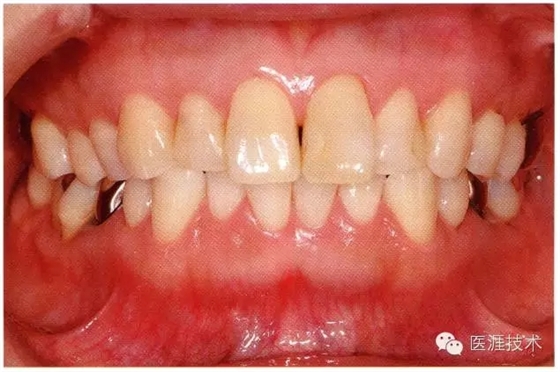

18歲男性的健康口腔內(nèi)部

圖為18歲男性,無特殊全身疾病,不抽煙。持續(xù)保養(yǎng)10年。牙菌斑控制比以前好,因刷牙稍稍過度臉頰側(cè)有牙齦萎縮傾向,但牙齒及牙周組織仍保健康。